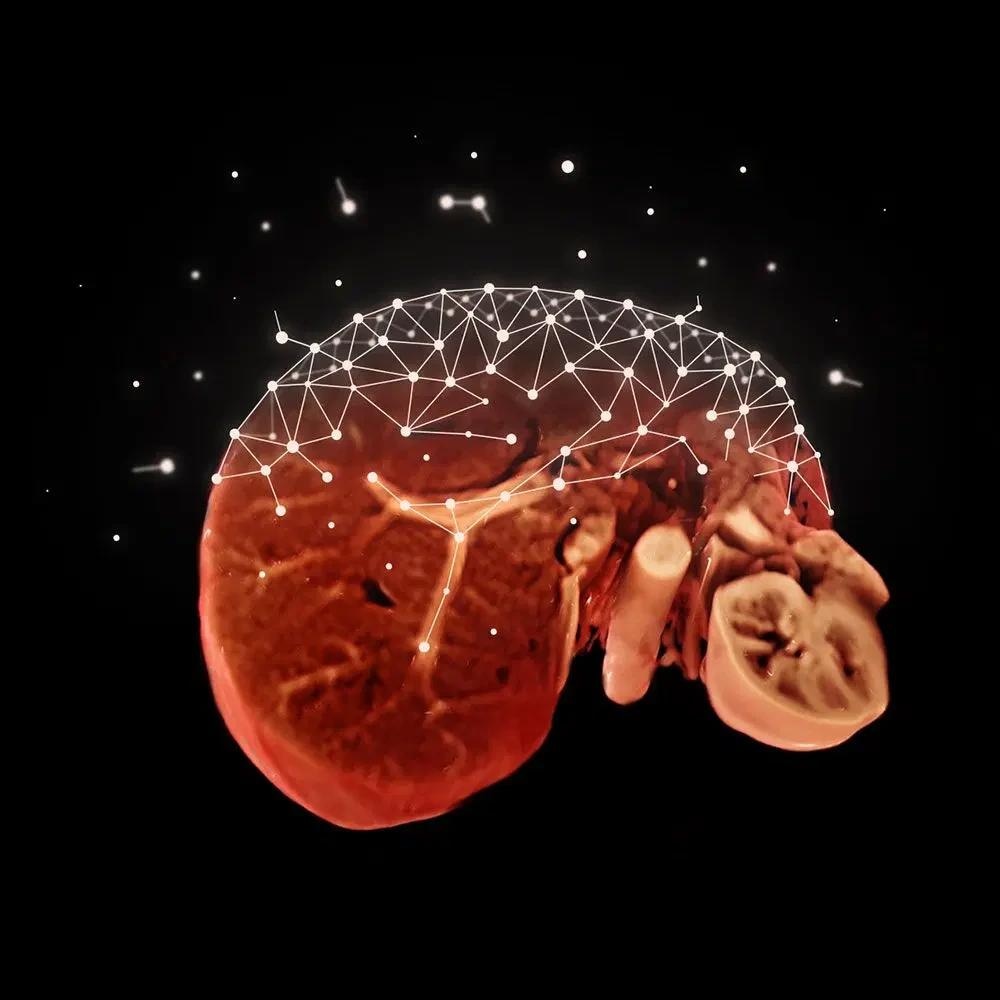

Free-breathing applications with Inline Compressed Sensing (available in Turbo Suite Elite)

Many kids, the elderly, or critically ill patients may be unable to maintain their breath long enough to undergo a liver examination with dynamic contrast enhancement or an entire cardiac examination.

Compressed Sensing heralds a paradigm shift in cardiac and body imaging therapeutic practice.

Expand the MR patient population eligible for MRI with Compressed Sensing GRASP-VIBE for free-breathing liver dynamics for patients with limited or no breath-hold capability and with Compressed Sensing Cardiac Cine for full free-breathing cardiac exams.

Embrace new 3T clinical capabilities with Inline Compressed Sensing

With Turbo Suite Elite, MAGNETOM Vida offers access to patients who have previously been excluded from MRI due to their medical condition or the exam’s exorbitantly complex nature. Compressed Sensing Cardiac Cine and Compressed Sensing GRASP-VIBE allow free-breathing exams, enhancing the patient experience while broadening the service offering.

Compressed Sensing GRASP-VIBE

GRASP-VIBE Compressed Sensing for dynamic liver imaging in free-breathing patients who cannot hold their breath reliably.

Compressed Sensing Cardiac Cine

Compressed Sensing Cardiac Cine for free-breathing Cardiac Cine imaging.